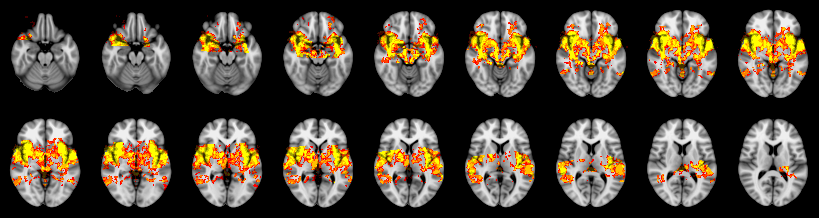

Pain study, TFCE, Uncorrected

Not combined

Face:

Hand:

Foot: